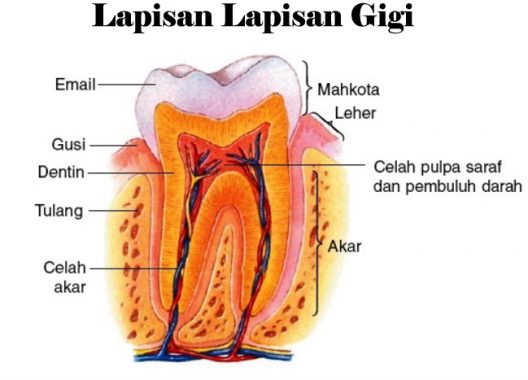

Mengenal Anatomi Gigi, Jenis-Jenis Gigi, dan Fungsi Tiap Bagiannya

Mengenal Anatomi Gigi, Jenis-Jenis Gigi, dan Fungsi Tiap Bagiannya

Struktur Anatomi Gigi - Pentingnya Menjaga Kesehatan Gigi Kita

Struktur Anatomi Gigi - Pentingnya Menjaga Kesehatan Gigi Kita

Gigi : Pengertian, Bagian, Jenis, Morfologi dan Strukturnya

Gigi : Pengertian, Bagian, Jenis, Morfologi dan Strukturnya

BAB I Anatomi Gigi

BAB I Anatomi Gigi

Struktur Dan Anatomi Gigi - [PDF Document]

Struktur Dan Anatomi Gigi - [PDF Document]

Pengertian Gigi - Bagian, Lapisan, Susunan, Macam, Contoh

Pengertian Gigi - Bagian, Lapisan, Susunan, Macam, Contoh